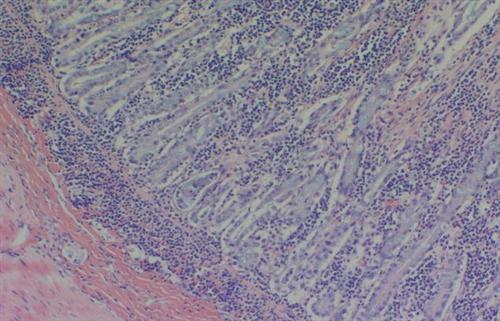

相关图片